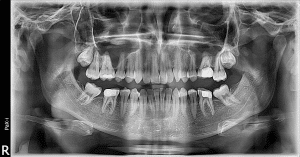

3-Dimentional X-Ray

At Redmond Family Smiles we use VATECH’s latest 3-D imaging device which combines extremely low radiation dose with the highest image quality using their latest patented digital sensor and software enhaced imaging technology. The machine is capable of acquiring CT scans of the teeth and jaws as well as Panoramic radiography, also called panoramic x-ray, which are the highest standard of care for imlant placement and root canal treatments. Using this technology, your dentist ensures all implants are placed at a safety distance to vital structures such as major nerves and blood vessels in the head and neck.

An x-ray (radiograph) is a noninvasive medical test that helps Dr Navid diagnose and treat dental conditions. Unlike a traditional x-ray where the film/x-ray detector is placed inside of the mouth, the film for a panoramic x-ray is contained inside of the machine. Therefore, it makes the imaging very convenient for individuals with strong gag reflex. Furthermore, the radiation dose a patient receives during this type of imaging is a fraction of Full Mouth Digital Radiography. At Redmond Family Smiles we use the state of the art Pax-I machine with a cutting edge technology that captures smallest details with lowest radiation dose.